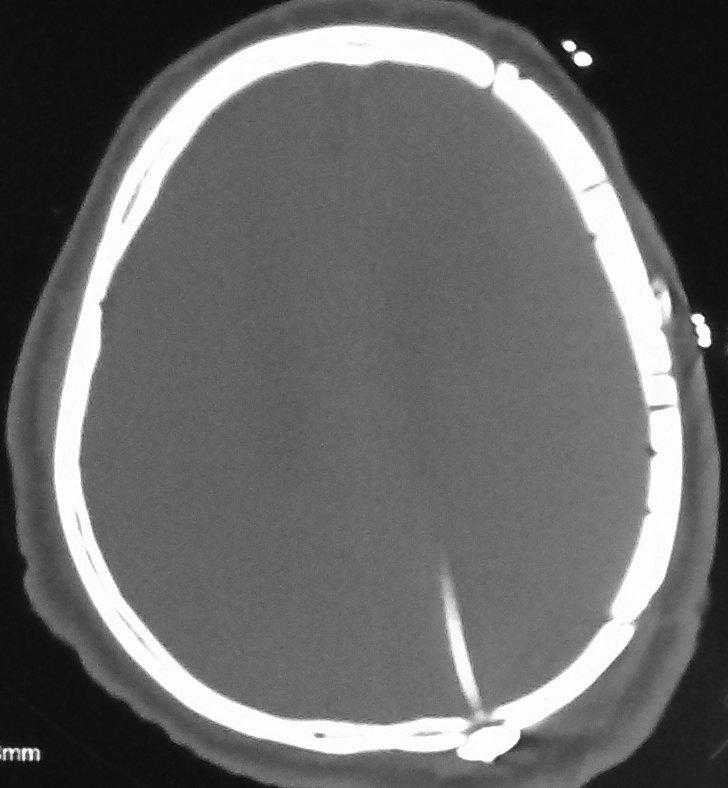

病例二:汪某某,男,49岁。修补材料:钛网。(患者家庭经济有限)

无缝隙人工骨精确植入: